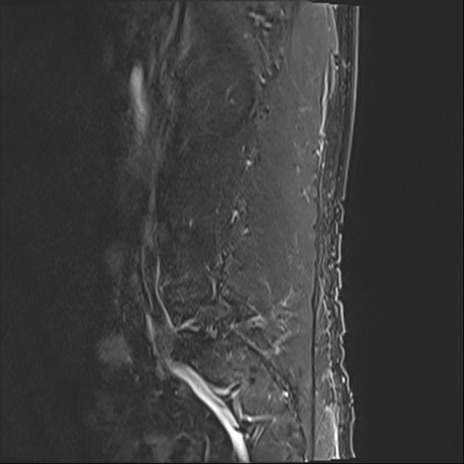

【整形】TIPS症例2 腰椎MRI STIR(矢状断像)

【症例】70歳代男性

【主訴】左下肢痛

【現病歴】2週間前くらいから腰痛、左下肢痛あり。左臀部から大腿、下腿外側のしびれが常時ある。歩行とともに同部位の痛みあり。

【身体所見】Lasegue70-/60+、Bragard-/±、PTR ±/±、ATR -/-、IP 5/5、TA 5/4、TS 5/5、EHL 右第1足趾なし/3、FHL 5/5、hypersthesia(-)、足背動脈触知良好

異常所見と診断は?